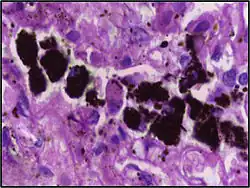

Micrograph showing hemosiderin-laden alveolar macrophages, as seen in a pulmonary hemorrhage. H&E stain.

Chronic pulmonary congestion Siderophages Brown-golden and refractile.[5] Alveoli[6]

• Heart failure

• Pulmonary hemorrhage

Siderophage (black arrow), and interstitium with edema, hemosiderin deposition (black arrow) and collagenous thickening, indicating heart failure.